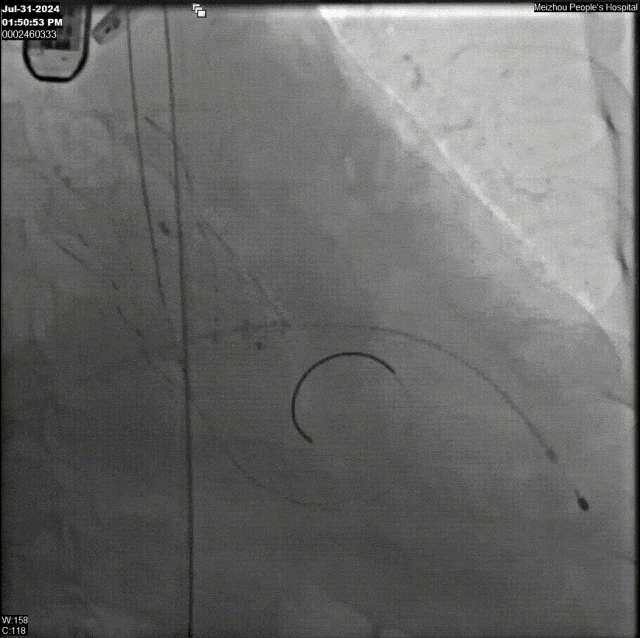

术中,手术团队精准操作器械缓缓进入患者体内,从右股动脉的主攻,到左股动脉与右肱动脉的巧妙辅助,形成了一套完美的“三路并进”策略,人工瓣膜在瓣环零位精准定位,辅助锚定器瞬间释放,确保了瓣膜的稳定植入与完美贴合。手术圆满完成,叠加封堵器械有效锚定人工主动脉瓣膜并成功释放,术后患者主动脉瓣反流明显改善。

最终造影观察:无PVL,冠脉正常显影,瓣膜最终位于瓣下约2mm

钟炜教授介绍,术中使用可回收的TaurusElite 主动脉瓣置换系统进行操作,该人工瓣膜底端最大直径为33mm,有更高的压缩比,同时它与锚定器械均为镍钛合金材料,2个器械的径向支撑力可以互相抵住对方,起到有效锚定,这也是这项技术能够成功的关键。